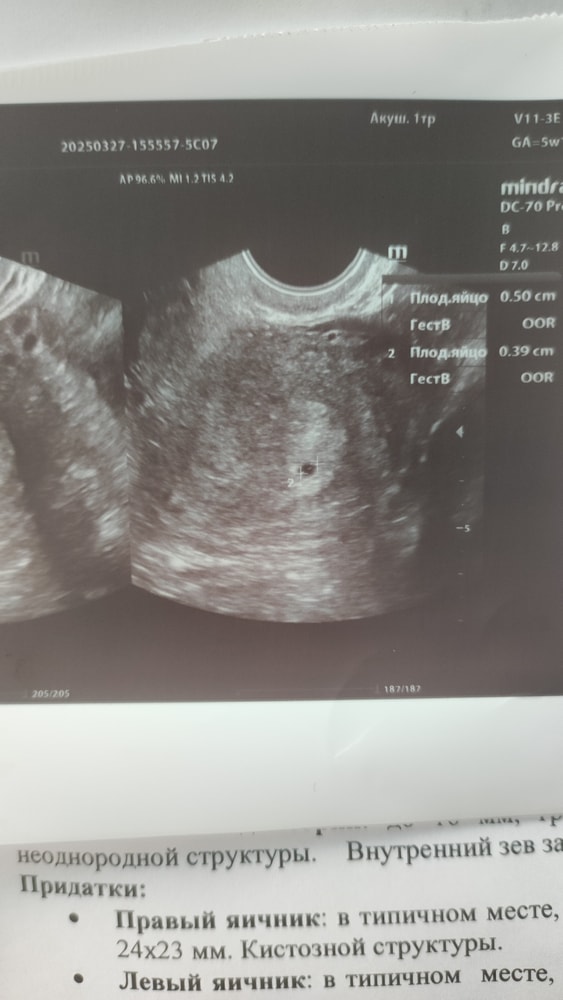

Беременность- 1 триместр ( только до 10 недель)Срок только 5н+1д, записана на УЗИ только через 4дня, но сегодня случились какие-то очень болючие прострелы в яичнике в котором ЖТ, даже заволновалась вдруг внематочная. Сильно больнее чем можно списать на работу ЖТ. Решила на авось заехать без записи на УЗИ платно, приняли. Так и появилась спонтанно первая фоточка, ПЯ 5мм)) и с яичником всё нормально, что за боли не понятно.